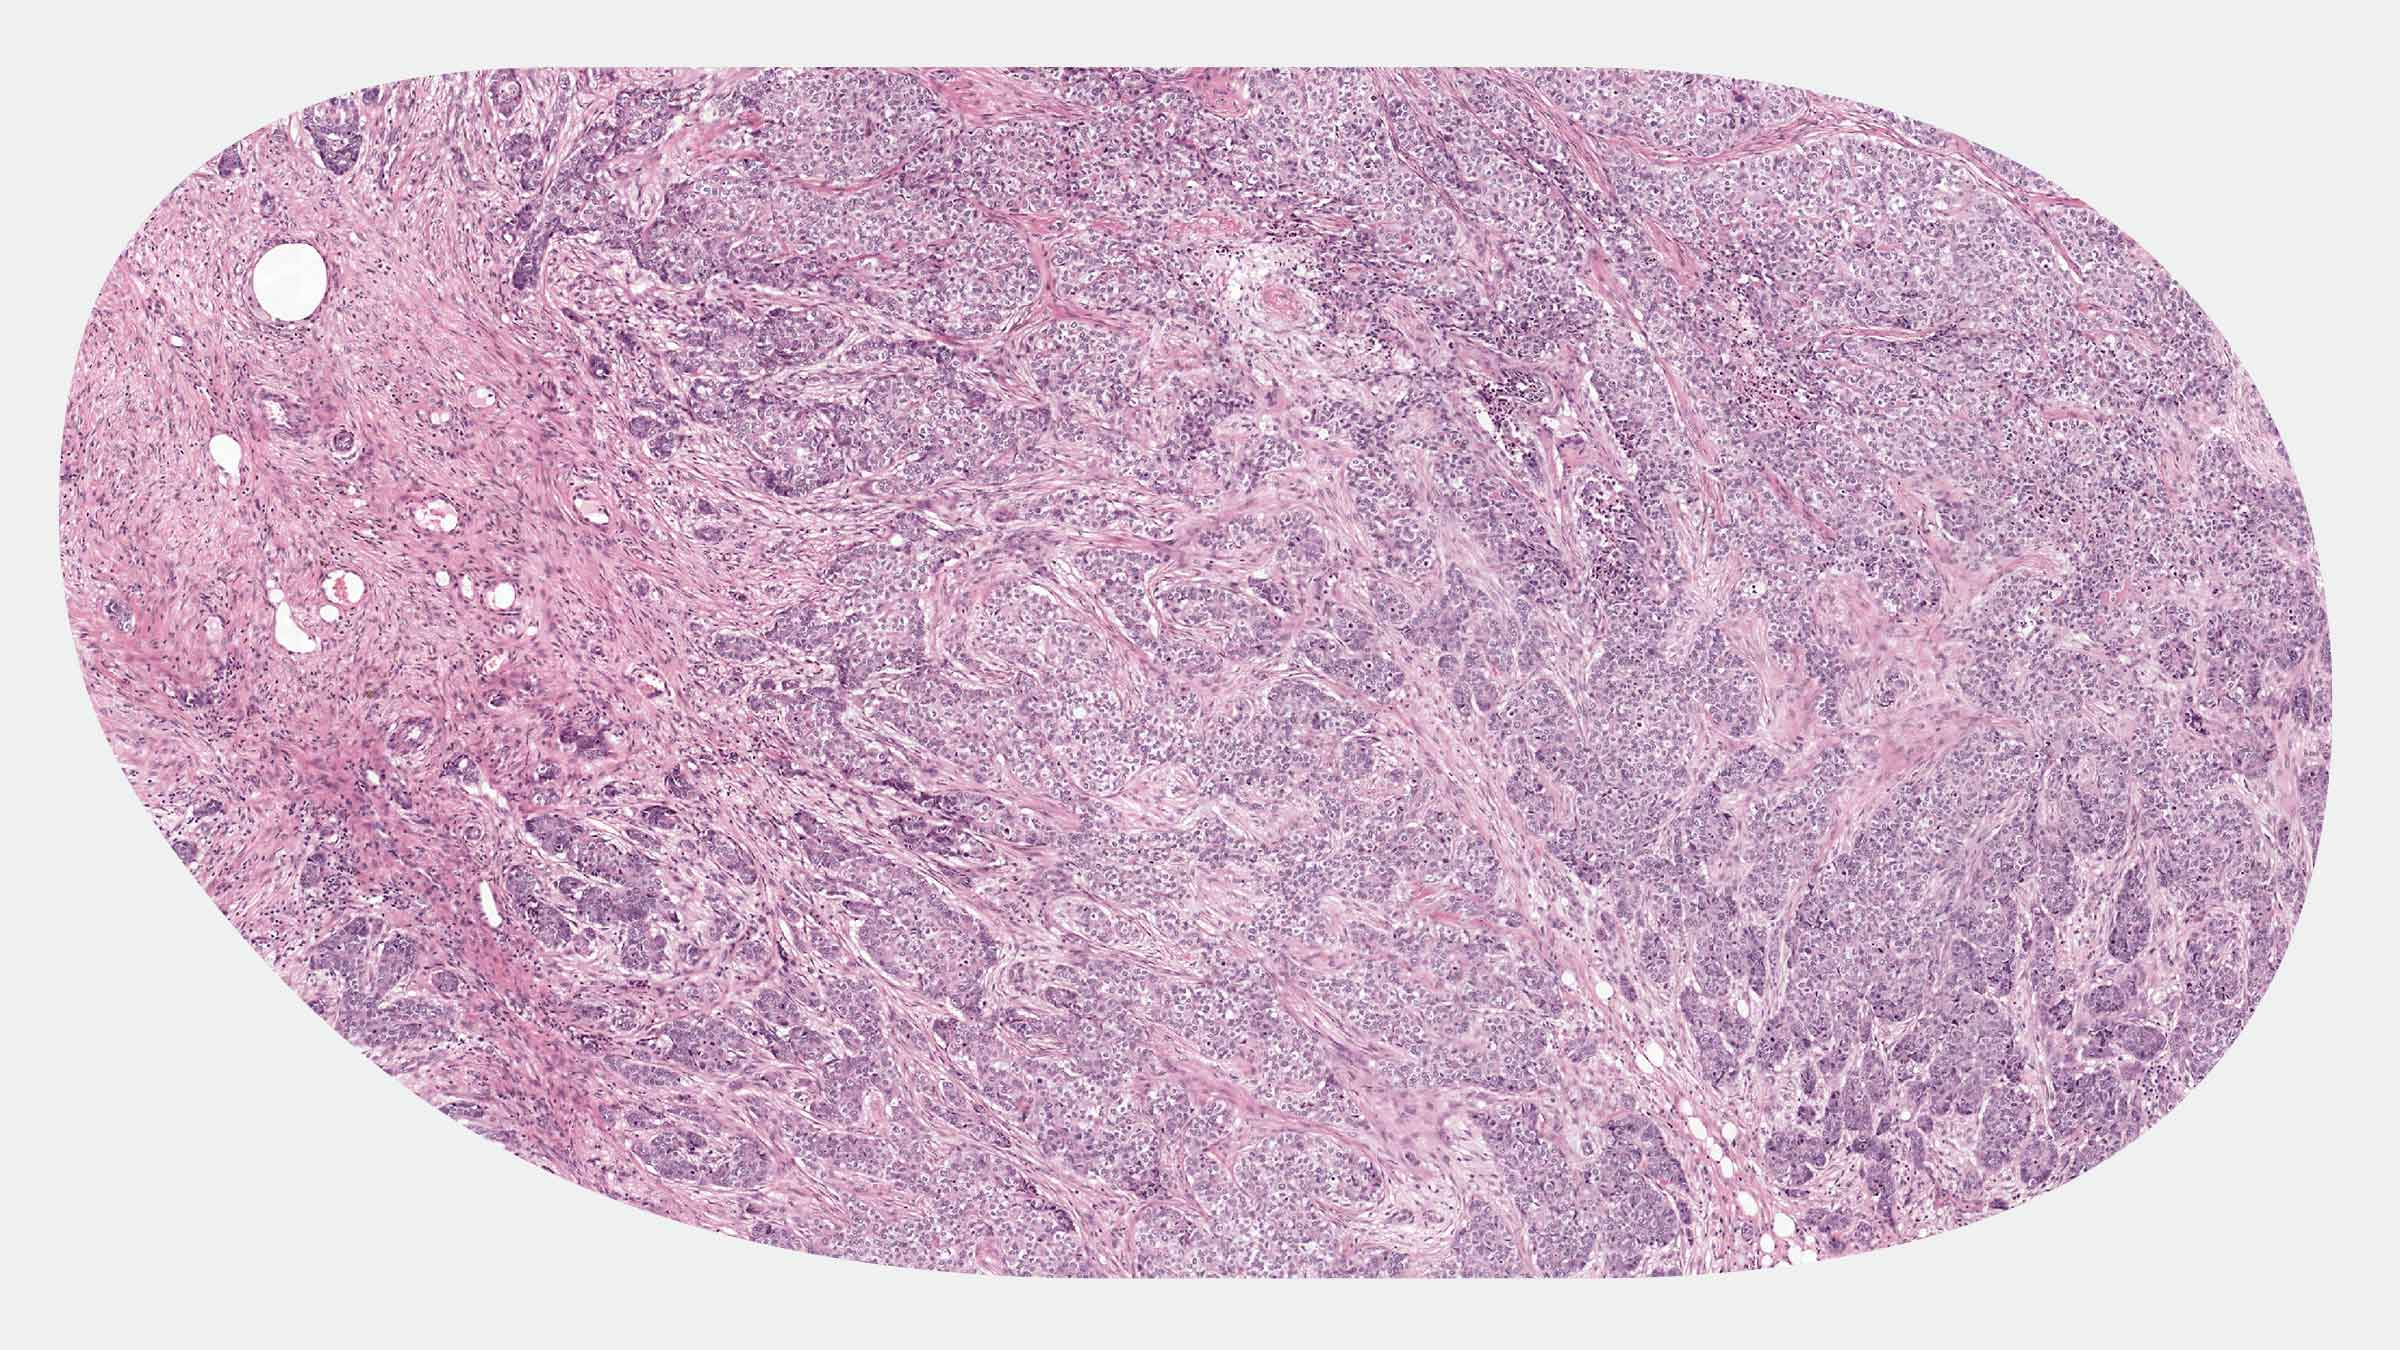

Traditioneel onderzoeken pathologen lichaamsweefsels op een glasplaatje onder een microscoop, om zo ziekten te diagnosticeren en behandelingsopties te begeleiden. Tegenwoordig worden deze glasplaatjes gescand in zeer hoge resolutie, waardoor digitale beeldanalyses mogelijk zijn.

Hematoxyline-eosinekleuring is de meest gebruikte methode om lichaamsweefsel op glasplaatjes te kleuren. Deze kleuring kenmerkt zich door blauwpaars en roze kleuren.